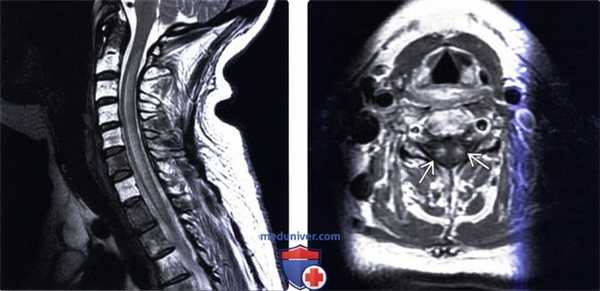

(Справа) Сагиттальный срез Т2-ВИ грудопоясничного отдела позвоночника отмечается умеренное расширение конуса спинного мозга, в центре которого определяется участок гиперинтенсивности Т2-сигнала, представляющий собой зону отека, захватывающую практически два позвоночных уровня.

(Слева) Представленное аксиальное Т2-ВИ этого же пациента подтверждает наличие очага патологического изменения Т2-сигнала, ограниченного практически только серым веществом спинного мозга. Объем конуса спинного мозга увеличен вследствие отека, однако изменений сигнала центрального канала спинного мозга, которые бы свидетельствовали о сирингогидромиелии, нет.